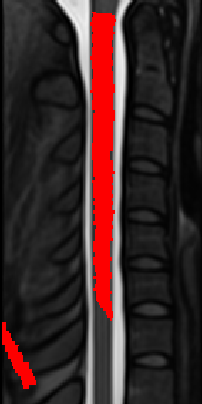

Actually, when applying the output warping field to the PAM50_seg image, I can reproduce the issue:

Full code:

sct_register_to_template -i t2_seg.nii.gz -s t2_seg.nii.gz -lrootlet t2_rootlets.nii.gz -ofolder ./ -c t2 -param step=1,type=seg,algo=syn,iter=0 -qc qc

sct_apply_transfo -i t2_seg.nii.gz -d $SCT_DIR/data/PAM50/template/PAM50_t2.nii.gz -w warp_curve2straight.nii.gz warp_anat2template.nii.gz -o t2_seg_PAM50.nii.gz -x nn

fsleyes $SCT_DIR/data/PAM50/template/PAM50_t2.nii.gz t2_seg_PAM50.nii.gz &

One possible avenue, is the warning I received when running sct_register_to_template:

Image /private/var/folders/qd/2g7h7921023d_rzm472bf8jm0000gn/T/sct_2026-04-21_13-58-03_register-to-template_5dxpqy_d/seg_bin_rpi_1mm_crop.nii.gz has different qform and sform matrices. This can produce incorrect results. Please use ‘sct_image -i /private/var/folders/qd/2g7h7921023d_rzm472bf8jm0000gn/T/sct_2026-04-21_13-58-03_register-to-template_5dxpqy_d/seg_bin_rpi_1mm_crop.nii.gz -header’ to check that both affine matrices are valid. Then, consider running either ‘sct_image -set-sform-to-qform’ or ‘sct_image -set-qform-to-sform’ to fix any discrepancies you may find.

Possibly related to the issue. I’m investigating… ![]()